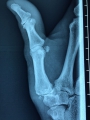

La rhizarthrose est une arthrose touchant la base du pouce, provoquant la destruction progressive du cartilage de l’articulation entre le trapèze et le premier métacarpien.

Chez un patient touché par une rhizarthrose, la base du pouce devient douloureuse, ainsi que les gestes nécessitant la pince entre pouce et index, et la main se déforme progressivement en Z.